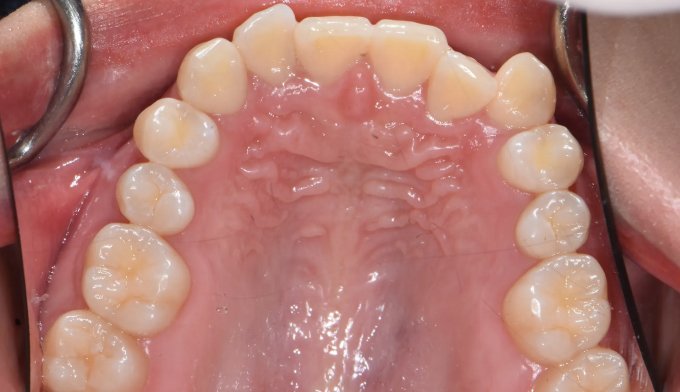

총 치료기간은 15개월 소요되었습니다.

거꾸로 물려있던 앞니를 앞으로 보내면서, 아래치열은 사랑니발치 후 미니스크류를 이용하여 후방이동시켰습니다.